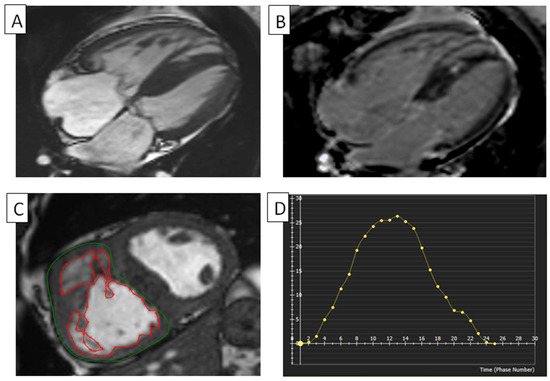

Figure 3.

RV in a tetralogy of Fallot. (A) Cine cMRI four-chamber view of a patient with TOF. The RV is mildly dilated and has mild RV hypertrophy. The LV has severe hypertrophy. (B) cMRI, with phase-sensitive inversion recovery and four-chamber view, of a patient with TOF, showing a dilated RV and RA. (C) Planimetry of RV. The RV myocardium’s epicardial (green) and endocardial (red) borders are manually traced at the end-diastole on this short-axis cMRI in a patient with TOF showing increased trabeculation in their right ventricle. (D) RV global radial strain in TOF. Radial strain values are usually positive. On the graph, the vertical axis shows the radial strain and the horizontal axis shows the time in milliseconds. RV, right ventricle; LV, left ventricle; cMRI, cardiac magnetic resonance imaging; TOF, tetralogy of Fallot.